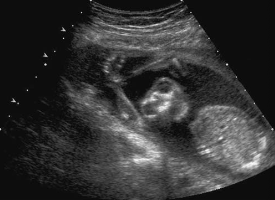

During a late second-trimester screening examination, what does this image of the fetal abdomen most likely show:

infantile polycystic disease

Which of the following conditions will likely occur because of this abnormality?

oligohydramnios